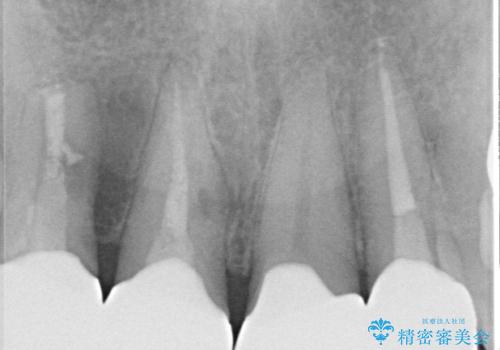

下顎の歯列は整えたいというご希望とは別に、上顎前歯にうずくような痛みや違和感があるとのことで、先に根管治療や歯根端切除術を行うこととしました。

痛みが消えた後に、より目立たない装置をご希望とのことで、下顎前歯の舌側矯正で部分矯正を行い、歯列が整い、上顎前歯歯根部の病変が消退したことを確認した上で、上顎前歯をオールセラミッククラウンにて補綴治療を行うこととしました。